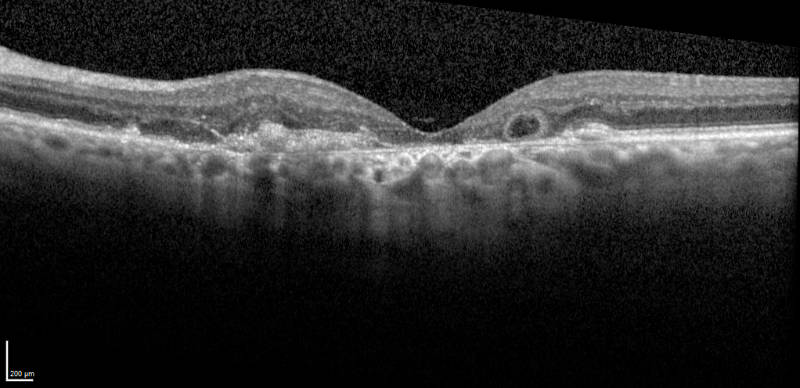

Discovery of Outer Retinal Tubulation with OCT

Zweifel SA, Engelbert M, Laud K, Margolis R, Spaide RF, Freund KB. Outer retinal tubulation: a novel optical coherence tomography finding. Arch Ophthalmol. 2009;127:1596-602.

Enhanced Depth Imaging with Ophthalmic Coherence Tomography

Enhanced Depth Imaging with Ophthalmic Coherence Tomography was a milestone in imaging and introduced by the foundations leading investigators.

Koizumi H, Spaide R, Fisher Y, Freund B, Klancnik J, Yannuzzi L

Three-dimensional evaluation of vitreomacular traction and epiretinal membrane using spectral- domain optical coherence tomography. AM J Ophthalmol 143(3):509-517, 2008.